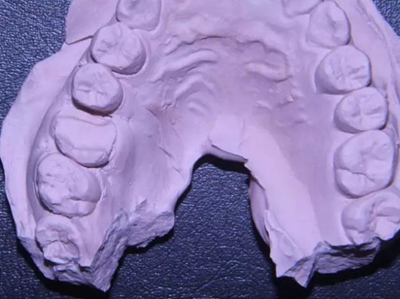

改良垂直褥式縫合關閉傷口,傷口無明顯滲血,高嵌體預備完畢后,硅橡膠取模,見邊緣清晰。灌注模型,模型上3MZ350XT分層堆塑高嵌體。